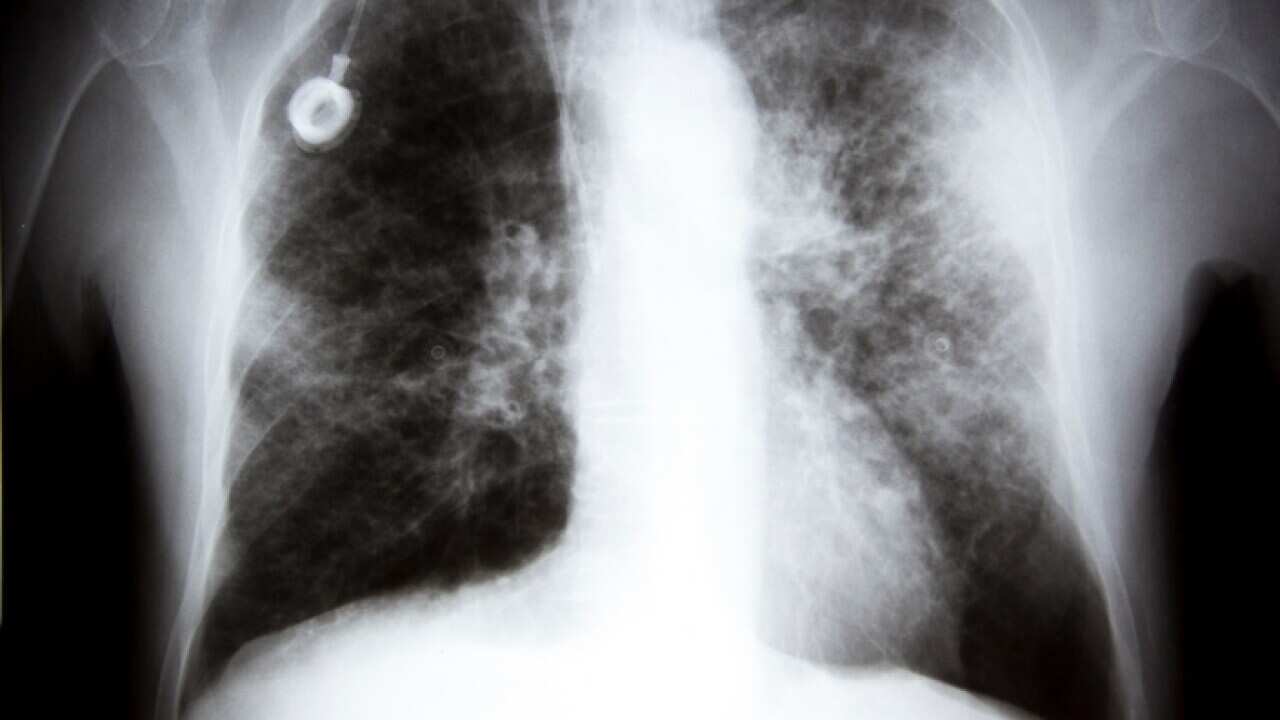

An X-ray showing lung cancer (Getty). Source: Getty Images

With lung cancer now recognised as the deadliest type of cancer in Australia, experts are urging a lifesaving rethink on how to detect it early.